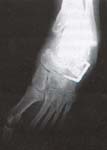

Se comparan los datos obtenidos en el preoperatorio y en el postoperatorio con una y otra técnica quirúrgica, reportando los valores medios en grados con el rango entre paréntesis para los siguiente ángulos:

- Ángulo talo-calcáneo en la proyección anteroposterior.

- Ángulo talo-calcáneo en la proyección lateral.

- Ángulo talo-primer metatarsiano en proyección anteroposterior.

- Ángulo talo-primer metatarsiano en proyección lateral.

- Ángulo calcáneo-quinto metatarsiano en proyección anteroposterior.

Las siguientes tablas resumen las medianas de los valores para los diferentes ángulos en los dos grupos.

Mediciones clínicas

Realizadas a partir de los videos que se obtienen durante las consultas en la clínica de marcha, permitieron observar que todos los pies incluidos en este trabajo fueron estabilizados mediante una y otra técnica operatoria. La recuperación del arco longitudinal del pie se observó en 5 de los 7 pies intervenidos con la técnica modificada y en 2 de 7 pies sometidos a la técnica convencional.

Los resultados obtenidos en este trabajo, especialmente la medida del ángulo talo-primer metatarsiano (que evalúa indirectamente la relación talo-navicular), sugieren que el uso de un injerto estructural para restaurar la longitud de la columna externa, así como un abordaje directo sobre la articulación talo-navicular permiten una corrección más adecuada del pie.

El ángulo entre el calcáneo y el quinto metatarsiano que busca evaluar el efecto sobre el abducto del antepié que tiene el alargamiento de la columna externa fue apenas discretamente más cercano a lo normal con la técnica modificada que con la convencional.

Finalmente, los ángulos talo-calcáneo que buscan evaluar la posición del retropié (varo o valgo) aparentemente no fueron diferentes en los dos grupos lo cual se esperaba dado que las modificaciones introducidas en la nueva técnica no incluyen tratamiento alguno sobre la articulación subastragalina.